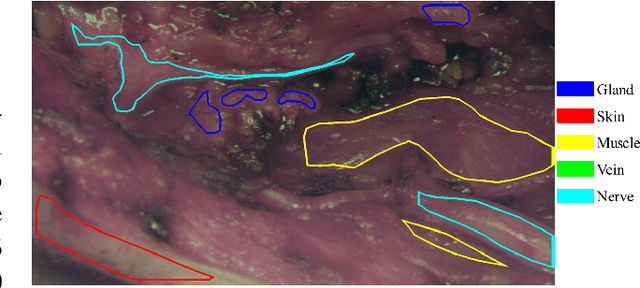

Abstract:In head and neck surgery, continuous intraoperative tissue differentiation is of great importance to avoid injury to sensitive structures such as nerves and vessels. Hyperspectral imaging (HSI) with neural network analysis could support the surgeon in tissue differentiation. A 3D Convolutional Neural Network with hyperspectral data in the range of $400-1000$ nm is used in this work. The acquisition system consisted of two multispectral snapshot cameras creating a stereo-HSI-system. For the analysis, 27 images with annotations of glandular tissue, nerve, muscle, skin and vein in 18 patients undergoing parotidectomy are included. Three patients are removed for evaluation following the leave-one-subject-out principle. The remaining images are used for training, with the data randomly divided into a training group and a validation group. In the validation, an overall accuracy of $98.7\%$ is achieved, indicating robust training. In the evaluation on the excluded patients, an overall accuracy of $83.4\%$ has been achieved showing good detection and identification abilities. The results clearly show that it is possible to achieve robust intraoperative tissue differentiation using hyperspectral imaging. Especially the high sensitivity in parotid or nerve tissue is of clinical importance. It is interesting to note that vein was often confused with muscle. This requires further analysis and shows that a very good and comprehensive data basis is essential. This is a major challenge, especially in surgery.